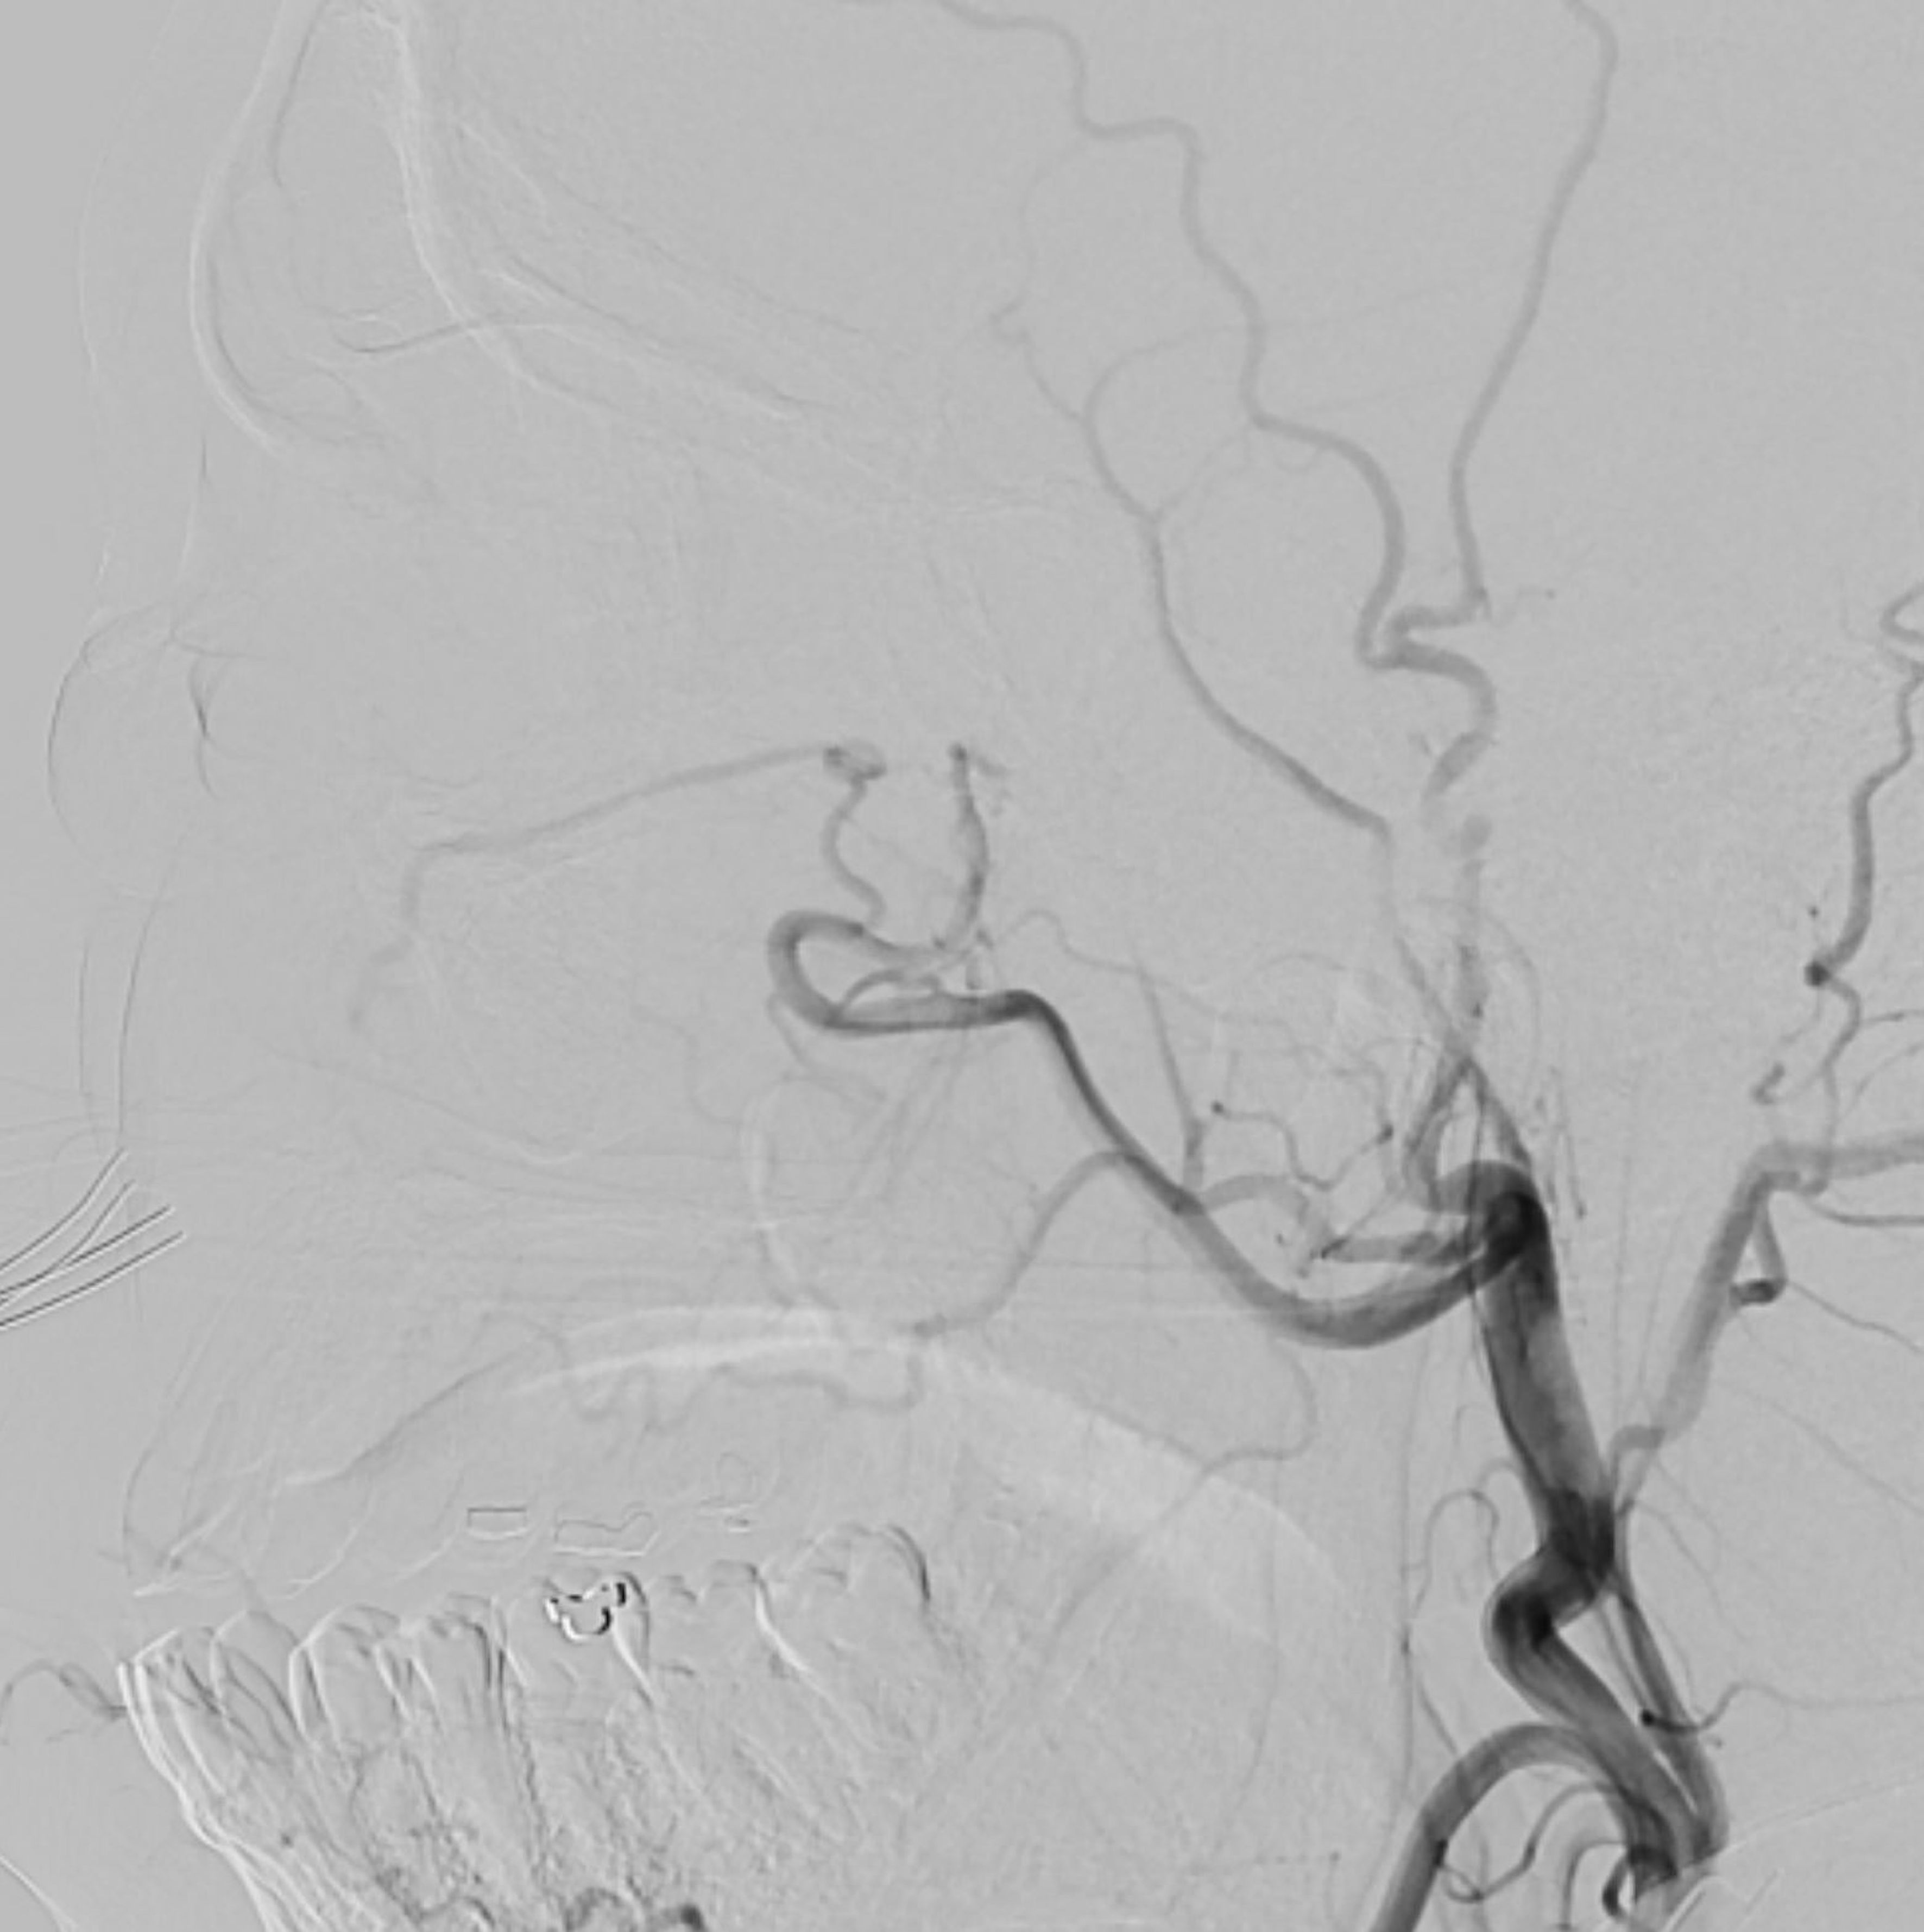

Figure 1. (A) Coronal transverse relaxation time short tau inversion recovery magnetic resonance image demonstrating a large venous aneurysm in the inferomedial left orbit. (B) Axial transverse relaxation time short tau inversion recovery magnetic resonance image demonstrating a dilated venous aneurysm in the posterior medial left orbit (arrow) with associated edema of the medial and lateral rectus muscles. (C, D) Longitudinal relaxation time post-gadolinium magnetic resonance coronal (C) and axial (D) images demonstrating enhancement of the venous aneurysm in the inferomedial left orbit. (EG) Computed tomography angiography with intravenous contrast in coronal (E), axial (F), and sagittal (G) views demonstrating enhancement of the venous aneurysm, which extends to the orbital apex.

A 48-year-old man presented with 1 month of blurry vision in the left eye without a history of trauma. His past medical history was significant for thyroid cancer in remission and hypothyroidism. On presentation to outside ophthalmology, he was noted to have left optic neuropathy with decreased vision (20/100), poor color vision, relative afferent pupillary defect, restricted extraocular motility, chemosis, eyelid edema, and elevated intraocular pressure. He had 5 mm of left-sided relative proptosis on Hertel exophthalmometry. Imaging, both CT and MRI, was initially read as a varix (Figure 1). He was treated for possible orbital cellulitis and possible thyroid eye disease with intravenous antibiotics and intravenous methylprednisolone, respectively, with no improvement. His proptosis and visual function worsened rapidly (Figure 2), and he was referred to our practice. Reassessment of his imaging raised doubts regarding the diagnosis, and an urgent angiogram was recommended. He was admitted, and six-vessel angiography demonstrated a left orbital arteriovenous fistula fed by three direct branches of the left ophthalmic artery with drainage to the superior ophthalmic vein (SOV) and no communication with the cavernous sinus (Figures 3, 4). MRI of the brain and orbits, and magnetic resonance angiography (MRA) and magnetic resonance venography (MRV) of the brain, demonstrated no evidence of vessel thrombosis or any previous connection to the cavernous sinus or other vasculature. Given the origin of the feeding arterioles off the proximal ophthalmic artery, an arterial approach was deemed to be high risk. Since the venous component of the fistula did not communicate with the cavernous sinus, this approach was not possible. A transvenous approach through the facial vein was also considered, but the indirect access would have made it difficult to guarantee occlusion at the fistula site or sites.